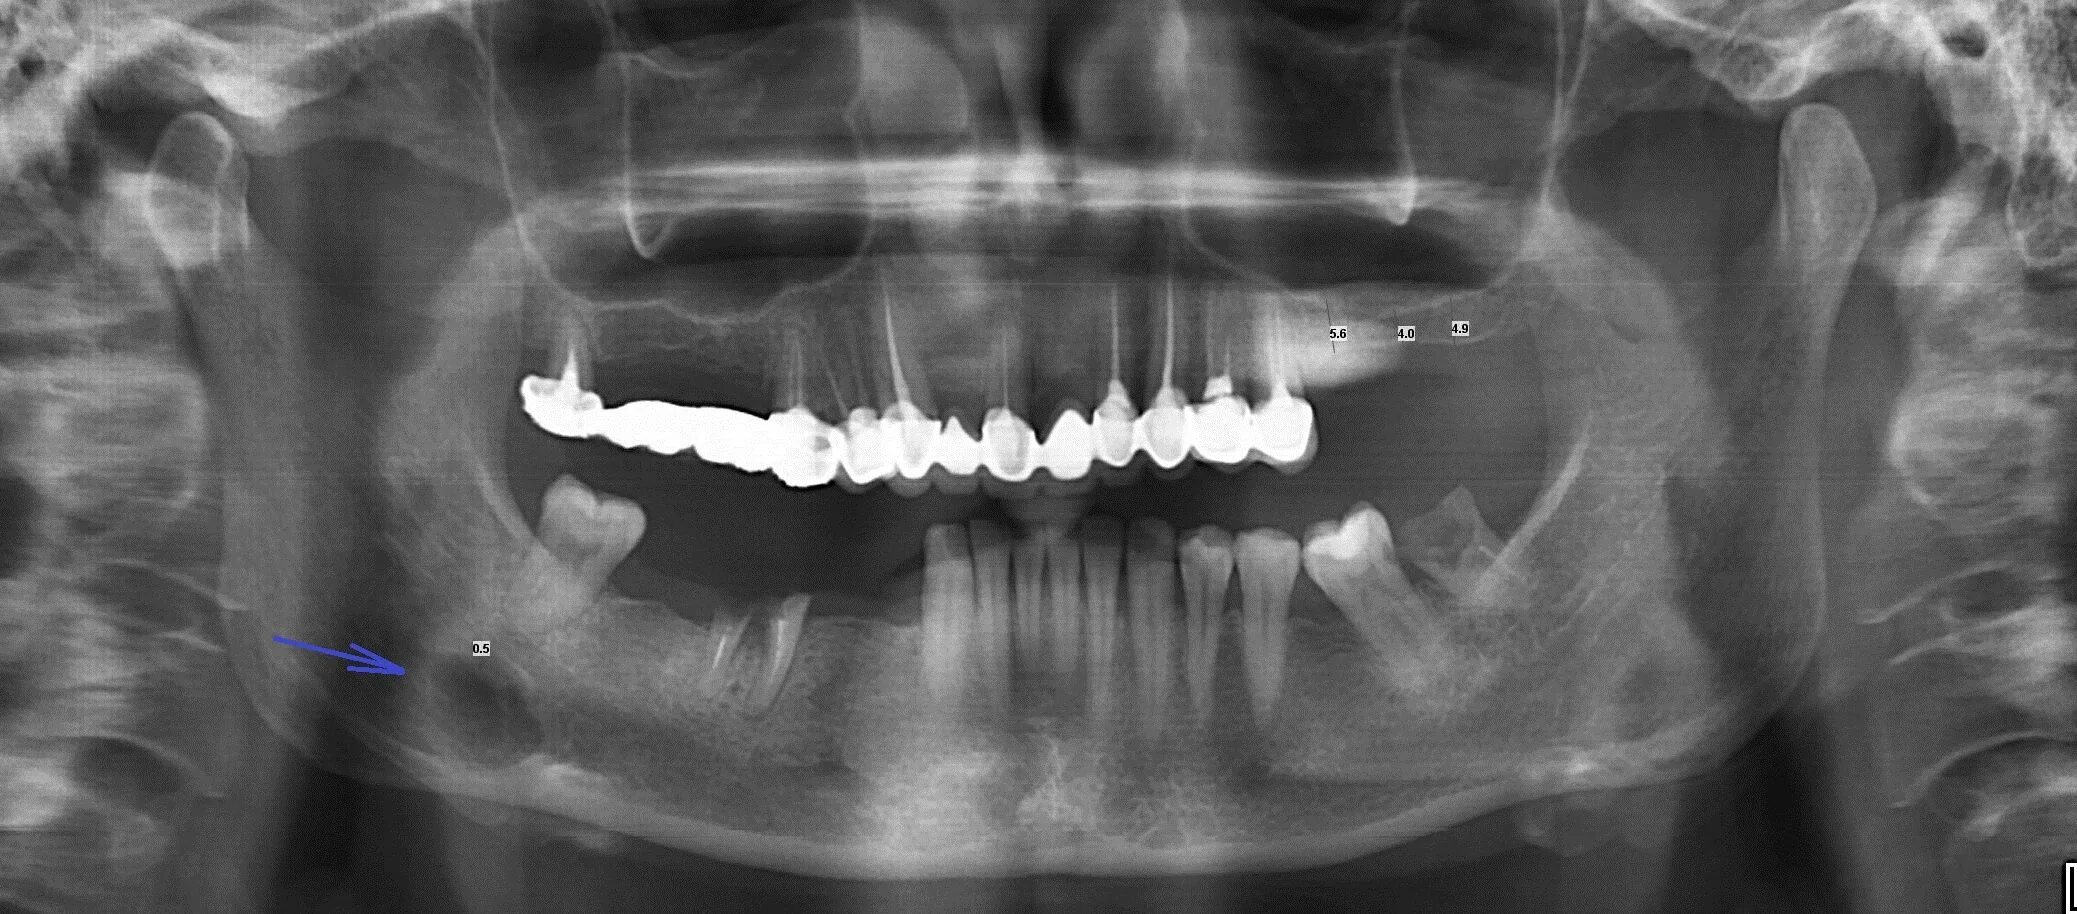

Снимок ротовой полости